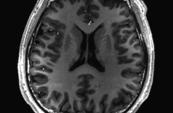

- Une équipe de recherche sous la direction d’Ariel Goldstein, du

département des sciences cognitives et cérébrales et de l'école de commerce de

l'université hébraïque de Jérusalem, a fait le lien entre les structures

acoustiques, les structures de la parole et les structures linguistiques au

niveau des mots, offrant ainsi un aperçu de la manière dont le cerveau traite

la parole quotidienne dans le monde réel. Elle a mis au point un cadre

informatique unifié pour explorer la base neuronale des conversations humaines.

L'étude a enregistré l'activité cérébrale

pendant 100 heures de conversations naturelles et ouvertes à l'aide d'une

technique appelée électro-corticographie (ECoG). Pour analyser les données

recueillies, l'équipe a utilisé le modèle de conversion de la parole en texte «

Whisper », qui permet de décomposer le langage en trois niveaux : les sons

simples, les schémas de parole et le sens des mots. Ces niveaux ont ensuite été

comparés à l'activité cérébrale à l'aide de modèles informatiques avancés.

Après avoir analysé les données, les

chercheurs ont constaté que le cadre pouvait prédire l'activité cérébrale avec

une grande précision. Même appliqué à des conversations qui ne faisaient pas

partie des données originelles, le modèle a correctement fait correspondre

différentes parties du cerveau à des fonctions linguistiques spécifiques.

IRM sectionnelle pondérée en T1 d'un cerveau humain sain

IRM sectionnelle pondérée en T1 d'un cerveau humain sain

Dr Goldstein : « Nos résultats nous aident à comprendre comment le cerveau traite les

conversations dans la vie réelle … En

reliant les différentes couches du langage, nous découvrons les mécanismes de

ce que nous faisons tous naturellement, à savoir parler et se comprendre les

uns les autres ».

Cette recherche a des applications pratiques

potentielles, allant de l'amélioration de la technologie de reconnaissance

vocale à la mise au point de meilleurs outils pour les personnes ayant des

difficultés de communication. Elle offre également de nouvelles perspectives

sur la manière dont le cerveau donne l'impression que la conversation se fait

sans effort, qu'il s'agisse de bavarder avec un ami ou de participer à un

débat.